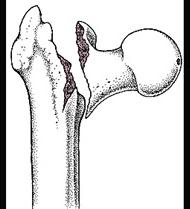

股骨转子间骨折(如图)容易发生的并发症是 ( )A、创伤性髋关节炎B、股骨头缺血性坏死C、损伤性骨化D、髋内翻畸形E、骨折不愈合

问题 股骨转子间骨折(如图)容易发生的并发症是 ( )

选项 A、创伤性髋关节炎 B、股骨头缺血性坏死 C、损伤性骨化 D、髋内翻畸形 E、骨折不愈合

答案 D